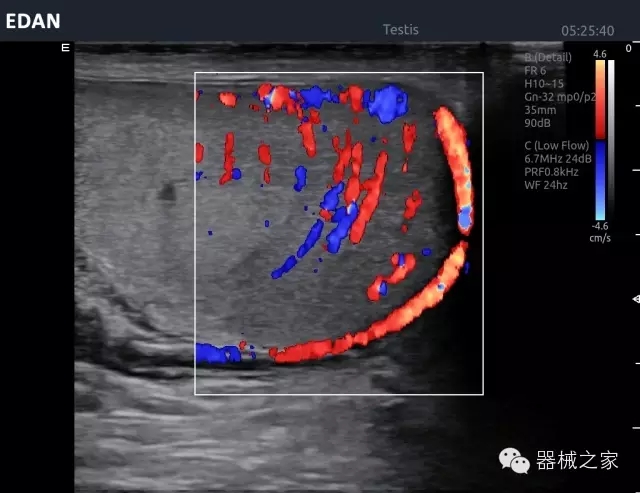

經典產品:Acclarix AX8

臨床圖片賞析

睪丸低速血流

臍帶血流

頸動脈頻譜

產品特點

·新視界、高效能、新體驗;

·別具匠心的獨特設計、創(chuàng)新工作流、強大的功能組合以滿足POC圖像的需求;

·15英寸高分辨率顯示器;

·10.1英寸防指紋觸摸屏;

·獨一無二的觸控式軌跡球;

·超聲模塊的便攜式設計;

·128物理通道;

·UPS持續(xù)供電;

多項前沿圖像技術

·復合成像 波束合成 頻率復合 噪聲抑制等;

穿刺針增強技術

·顯著增強針體 清晰識別結構、位置等比鄰關系;

多種成像模式

·梯形成像 寬景成像 3D成像 特征成像等;

CFDA注冊證編號

·粵械注準20152230912